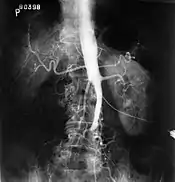

El síndrome de Leriche o enfermedad oclusiva aortoiliaca es una condición patológica que consiste en la oclusión ateroesclerótica que compromete la aorta abdominal y/o las arterias ilíacas comunes.

![]() | ||